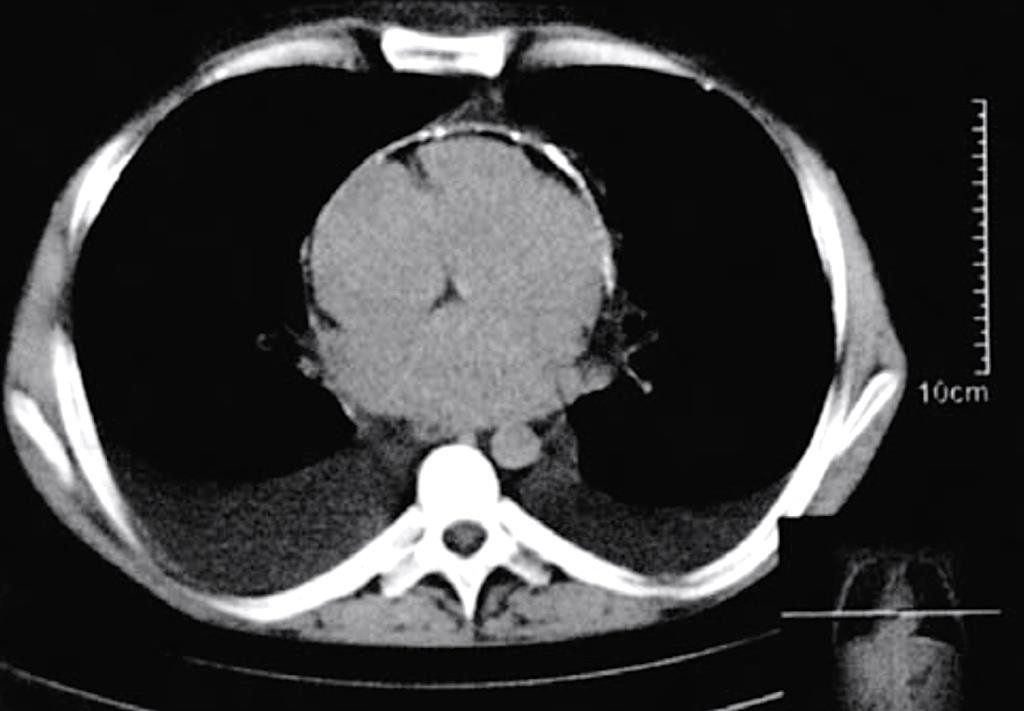

Развитие «панцирного» сердца происходит в 25% случаев констриктивного перикардита. Обызвествленные участки лучше определяются на боковой и передней косой проекциях (Приложение А3, рис. 10) [1, 3].

Благодаря высокой разрешающей способности, позволяющей выявлять утолщение листков перикарда от 2 мм (что примерно в 2 раза больше толщины неизмененного перикарда), КТ используется для диагностики констриктивного перикардита с кальцификацией или без нее [1].

Высокая разрешающая способность КТ играет важную роль в дифференциальной диагностике констриктивного перикардита и рестриктивной кардиомиопатии. Выявляемое утолщение париетального листка перикарда в среднем от 4 до 20 мм позволяет разграничить эти состояния [153]. Однако у 28% (18% при аутопсии) больных с констриктивным перикардитом не определяется утолщение перикарда [154].

Кальцификация перикарда, выраженная в той или иной степени, визуализируется у 50% пациентов. При этом КТ позволяет, в отличие от ЭхоКГ, визуализировать отложение кальция на любой поверхности сердца, особенно в местах с большим содержанием эпикардиального жира (атриовентрикулярные борозды и основание сердца) (Приложение А3, рис. 11) [154, 155].

Косвенными признаками констриктивного перикардита будут: уменьшение и циркулярная деформация правого и левого желудочков. Нарушение диастолической функции правого желудочка проявляется расширением нижней полой и печеночных вен, гепатоспленомегалией, асцитом и плевральным выпотом.